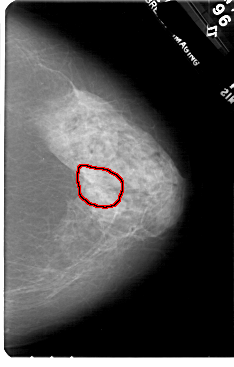

FILE: A_1720_1.RIGHT_MLO.OVERLAY

TOTAL_ABNORMALITIES 1

ABNORMALITY 1

LESION_TYPE MASS SHAPE ARCHITECTURAL_DISTORTION MARGINS SPICULATED

ASSESSMENT 4

SUBTLETY 2

PATHOLOGY MALIGNANT

TOTAL_OUTLINES 1

BOUNDARY